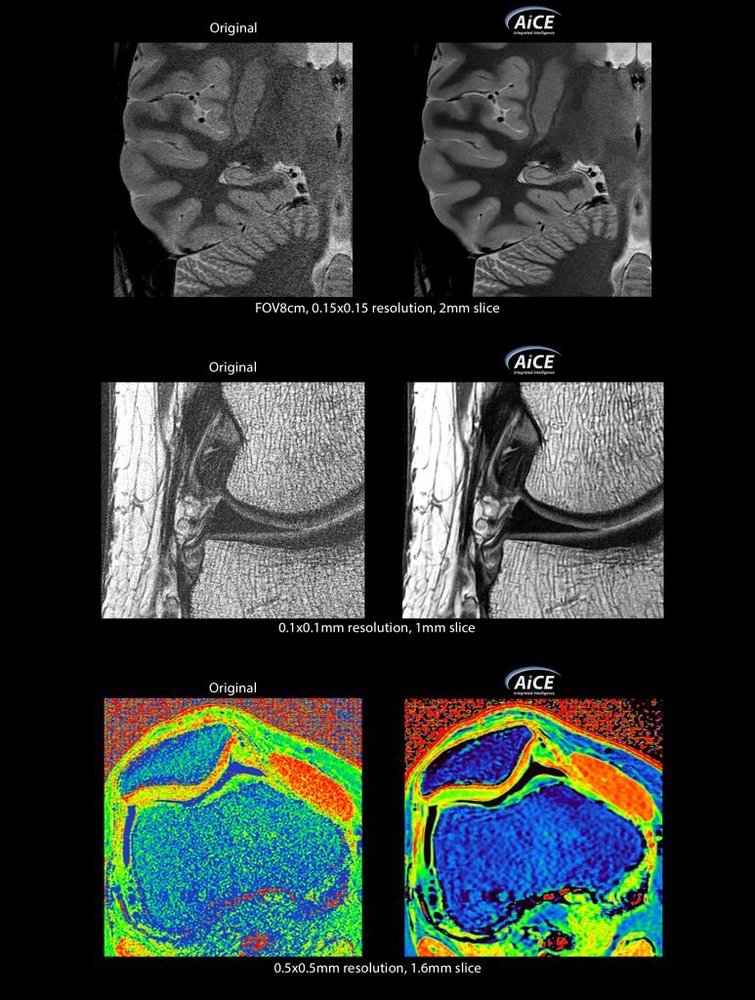

KI-optimiertes Arbeiten und modernste 3T-Technologie machen den Vantage Galan 3T von Canon Medical aus. Canons KI-Anwendung AiCE, kurz für Advanced intelligent Clear-Imagequality Engine, entfernt intelligent das Rauschen und führt zu einer Verbesserung des SNR (Signal-Rausch-Verhältnis). Mit Hilfe der Deep Learning Technologie gelingen besonders klare und deutliche Bilder. Insgesamt ermöglicht die KI-Unterstützung des Vantage Galan 3T somit nicht nur eine höhere Auflösung der Bilder, sondern verkürzt in vielen Fällen auch die Aufnahmezeit.

Mit der PURERF-Technologie und der PUREGradienten-Technologie werden das SNR um bis zu 20% verbessert und Diffusionsbilder optimiert.

• AiCE KI-Technologie zur Entfernung von Bildrauschen und Verbesserung des SNR

• Verbesserung des SNR um bis zu 20% durch PURERF-Technologie

• Optimierung von Diffusionsbildern durch PUREGradienten-Technologie